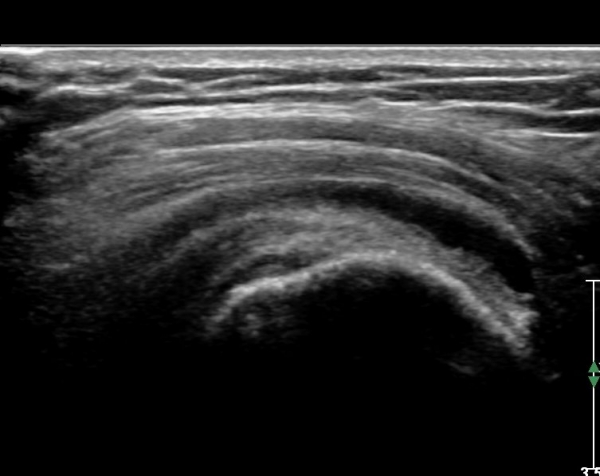

ŽÃËÀÚ¸¦ Á¶±Ý ¸»´ÜÀ¸·Î À̵¿ÇÏ´Ï ¿À±¸µ¹±â°ßºÀÀÎ´ë °ßºÀ ºÎÂøºÎ °ñ±ØÀÌ °üÂûµÇ°í ÀÎ´ë ½ÉÃþºÎ¿¡ ¼ö¾×Àú·ù°¡ ÀÖ¾î ¸¸¼ºÀûÀÎ Ãæµ¹À» ÃßÁ¤ÇÒ ¼ö ÀÖ´Ù(»çÁø 2).

ŽÃËÀÚ¸¦ Á»´õ ¸»´ÜÀ¸·Î À̵¿ ÈÄ(¶Ç´Â ¾Æ·¡·Î ±â¿ïÀÎ ÈÄ) ³»ÃøºÎ¸¦ Á¶ÀýÇÏ´Ï °ß°©ÇÏ±Ù°Ç Ç¥ÃþÀ¸·Î Á¡¾×³¶³» ¼ö¾×Àú·ù°¡ °üÂûµÈ´Ù(»çÁö 3, 4). ŽÃËÀÚ¸¦ Á¶Á¤ÇÏ´Ï ÀÌµÎ¹Ú°Ç ÁÖÀ§ ¼ö¾× Àú·ù¿Í Á¡¾×³¶³» ¼ö¾×Àú·ù°¡ °üÂûµÇ¾î Á¡¾×³¶¿°°ú Ȱ¾×¸·¿°ÀÌ ÀÖÀ½À» ¾Ë ¼ö ÀÖ´Ù(»çÁø 5).